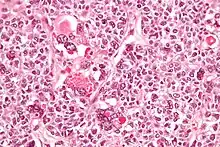

| Micrograph of a juvenile granulosa cell tumour with hyaline globules. H&E stain. | |

Histology

Juvenile granulosa cell tumors can be distinguished from adult granulosa cell tumors on histology by their abundant, eosinophilic cytoplasm; primitive, highly mitotic nuclei in polygonal cells; and disorganized follicles.[12][13]